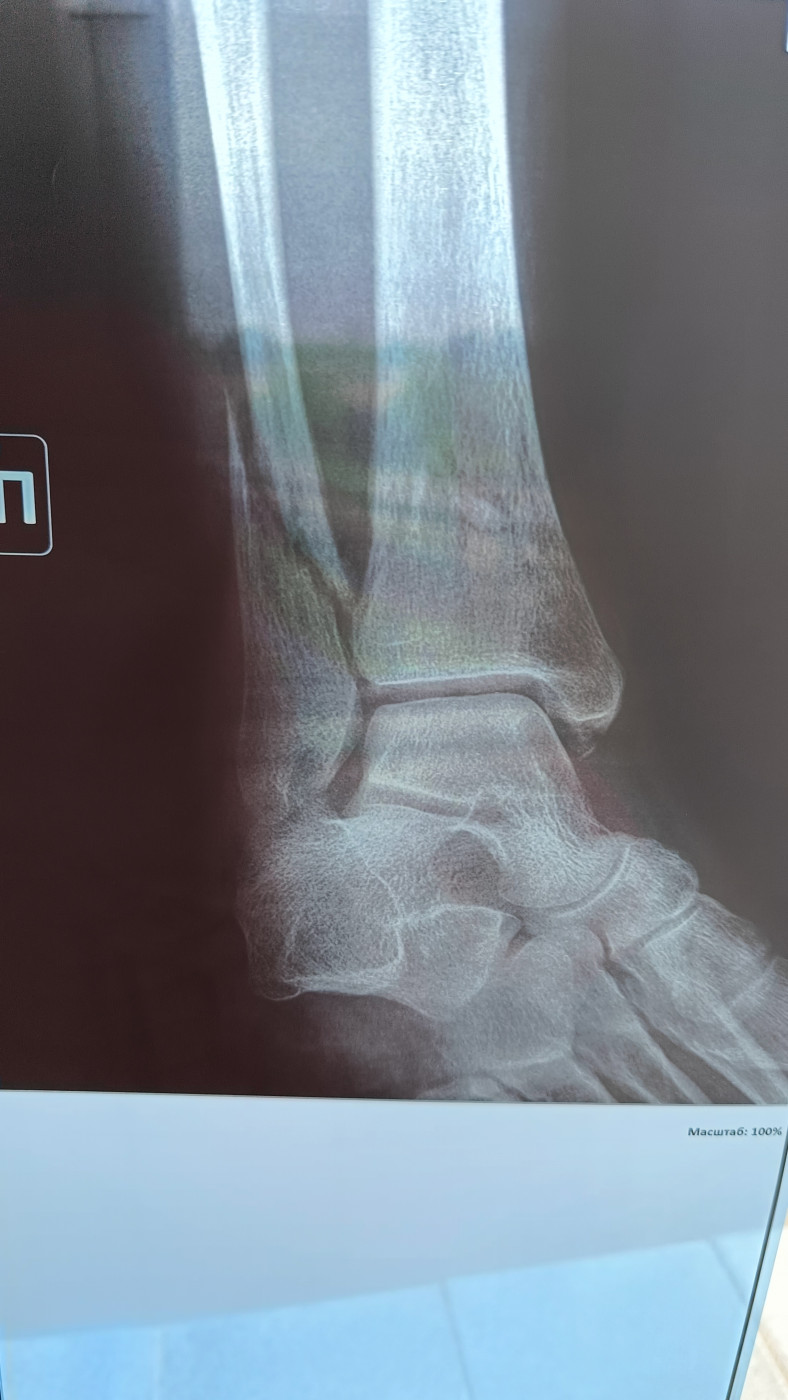

Вывих голеностопа   1 ответ

Здравствуйте. При занятиях спортом неправильно встал на голеностоп. Была резкая боль, затем утихла. Домой дошел сам. С утра появилась припухлость и болевые ощущения при наступлении на стопу. Подскажите, пожалуйста, это может быть разрыв связок или растяжение? Фото прикладываю